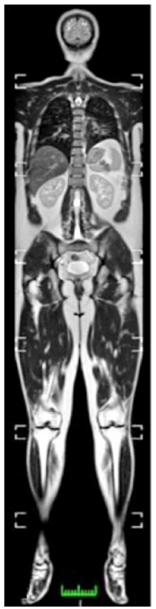

Observe a imagem a seguir:

A ressonância magnética de corpo inteiro vem ganhando cada vez mais importância na reumatologia, principalmente no que se refere ao diagnóstico, acompanhamento e avaliação da resposta ao tratamento.

Em relação às indicações para o uso de ressonância magnética de corpo inteiro em espondilite anquilosante (EA), assinale a afirmativa correta.